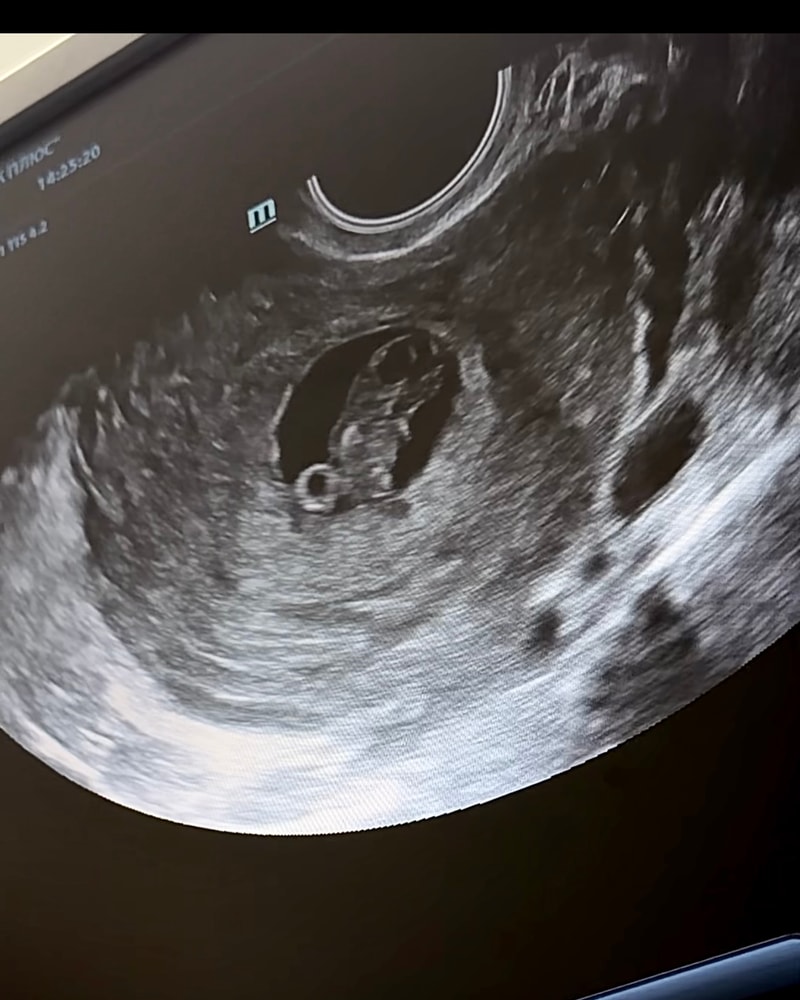

Нам 8 недель 4 дня))

Сердечко ритмичное, ктр 21мм, срок 8 недель 4 дня, мы уже двигаем ручками и ножками))) это просто чудо,такой уже маленький большой человек🥹🙏🏻